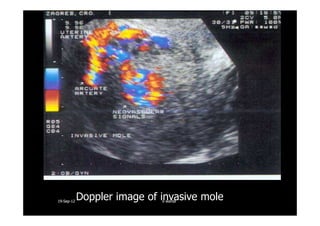

A case of invasive mole: inside the uterine cavity the typicalA case of invasive mole: inside the uterine cavity the typical

““snow stormsnow storm”” appearance can be detected, The location ofappearance can be detected, The location of

blood flow suggest an invasive mole.blood flow suggest an invasive mole.

Doppler image of invasive mole1919--SepSep--1212 o wardao warda